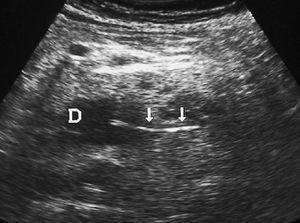

El duodeno es una localización infrecuente de diverticulitis. La imagen radiológica consiste en un engrosamiento de la pared del duodeno asociado a un divertículo, en ocasiones con un enterolito en su interior, con inflamación de la grasa adyacente16 (fig. 9).

Fig. 9--Diverticulitis duodenal. (A) En la ecografía se observa un divertículo (flechas) con engrosamiento de pared duodenal (D) y alteración de la grasa adyacente (*). (B) Tomografía computarizada de otro paciente con inflamación de divertículo duodenal. Se oberva una lesión quística (punta de flecha) de pared gruesa y borrosa, con material en su interior. P: Páncreas.